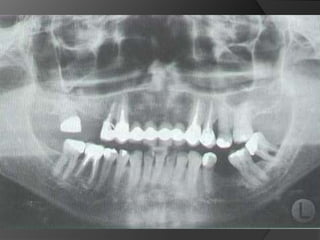

Diagnóstico y Planificación MultidisciplinariaHistoria ClínicaAnamnesisFotografía clínica Montaje modelos de estudioEncerados DiagnósticosEvaluación Radiográfica Radiografías PeriapicalesRadiografía PanorámicaEvaluación DentalEvaluación PeriodontalEvaluación EndodónticaEvaluación OclusalEvaluación Articular?

Diagnóstico y PlanificaciónMultidisciplinariaHistoria ClínicaAnamnesisFotografía clínica Montaje modelos de estudioEncerados DiagnósticosEvaluación Radiográfica Radiografías PeriapicalesRadiografía PanorámicaEvaluación DentalEvaluación PeriodontalEvaluación EndodónticaEvaluación OclusalEvaluación Articular?